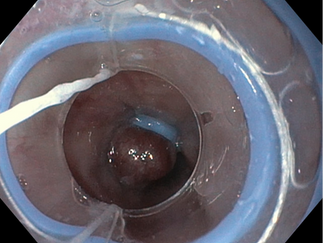

Ein Bandligationssystem (Bld 3a) wird an der Spitze des Endoskops (3b) angebracht, das in die Speiseröhre (3c) eingeführt wird, um nach Varizen (3d) zu suchen ; diese werden mit dem Gerät (3e und 3f) ligiert. In einer Sitzung können drei oder vier Varizen ligiert werden.

Unten von links: Ösophagusvarizen. Ligatur der Varizen. Ligierte Varizen.